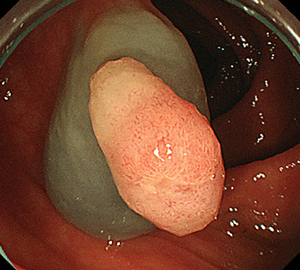

3:病変をスネアに通します。3:病変をスネアに通します。

4:周囲の正常粘膜をしっかり入れながら、病変を絞扼していき…4:周囲の正常粘膜をしっかり入れながら、病変を絞扼していき…

5:切除します。切除検体は吸引回収し、病理検査を行います5:切除します。切除検体は吸引回収し、病理検査を行います。